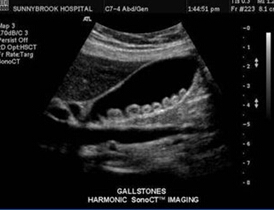

胆囊结石 ( calculus of gallbladder;Cholecystolithiasis )

别名: 胆囊结石;calculus cholecystitis;结石性胆囊炎